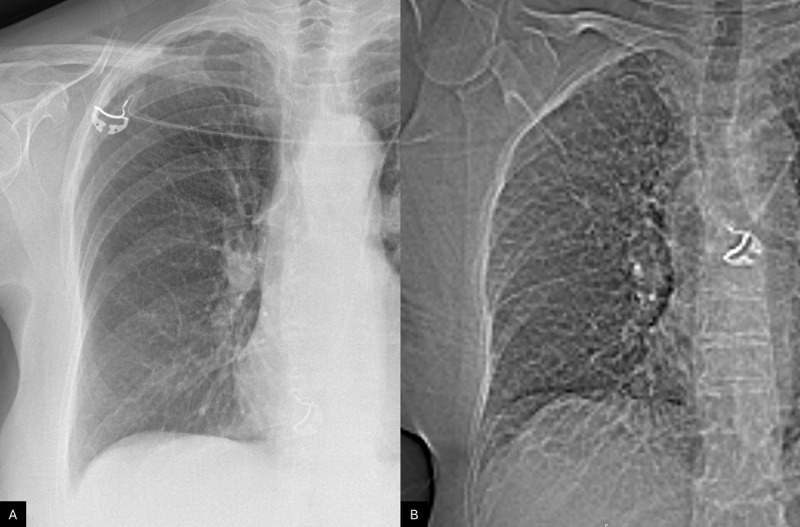

Teaching point: Transient interlobular septal nodules displaying a characteristic branched 'pearl-like' pattern may reflect acute pulmonary lymphatic overload and should not be mistaken for other common pathological processes.

教学要点:短暂性小叶间隔结节表现为特征性的“珍珠样”分支,可能反映急性肺淋巴负荷过重,不应与其他常见病理过程相混淆。